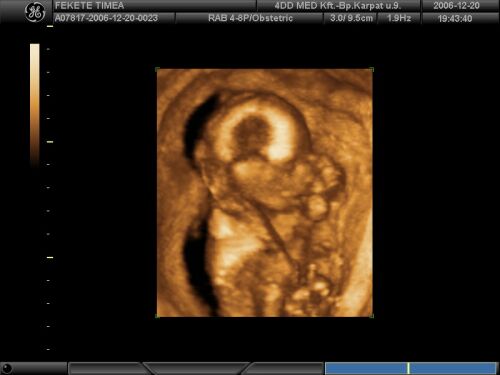

Timi! Livike nagyon édi azon a képen!! Mekkora haja van, és milyen szöszke lett!!!!! Hogy megy a suli?